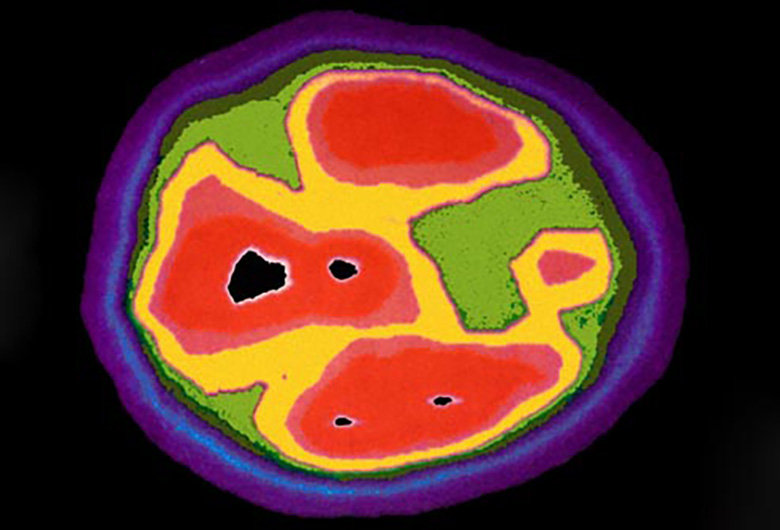

Bệnh tự kỷ ảnh hưởng đến não như thế nào? Bệnh tự kỷ ảnh hưởng đến các bộ phận của não điều khiển cảm xúc, giao tiếp và vận động cơ thể. Trong năm đầu đời, một số trẻ em bị hội chứng tự kỷ có đầu lớn bất thường, đó có thể là do vấn đề với sự phát triển não. Gen bất thường, di truyền trong gia đình, có liên quan đến chức năng kém ở một số bộ phận của não. Các nhà nghiên cứu hy vọng sẽ tìm ra cách để chẩn đoán bệnh tự kỷ thông qua chụp quét não.